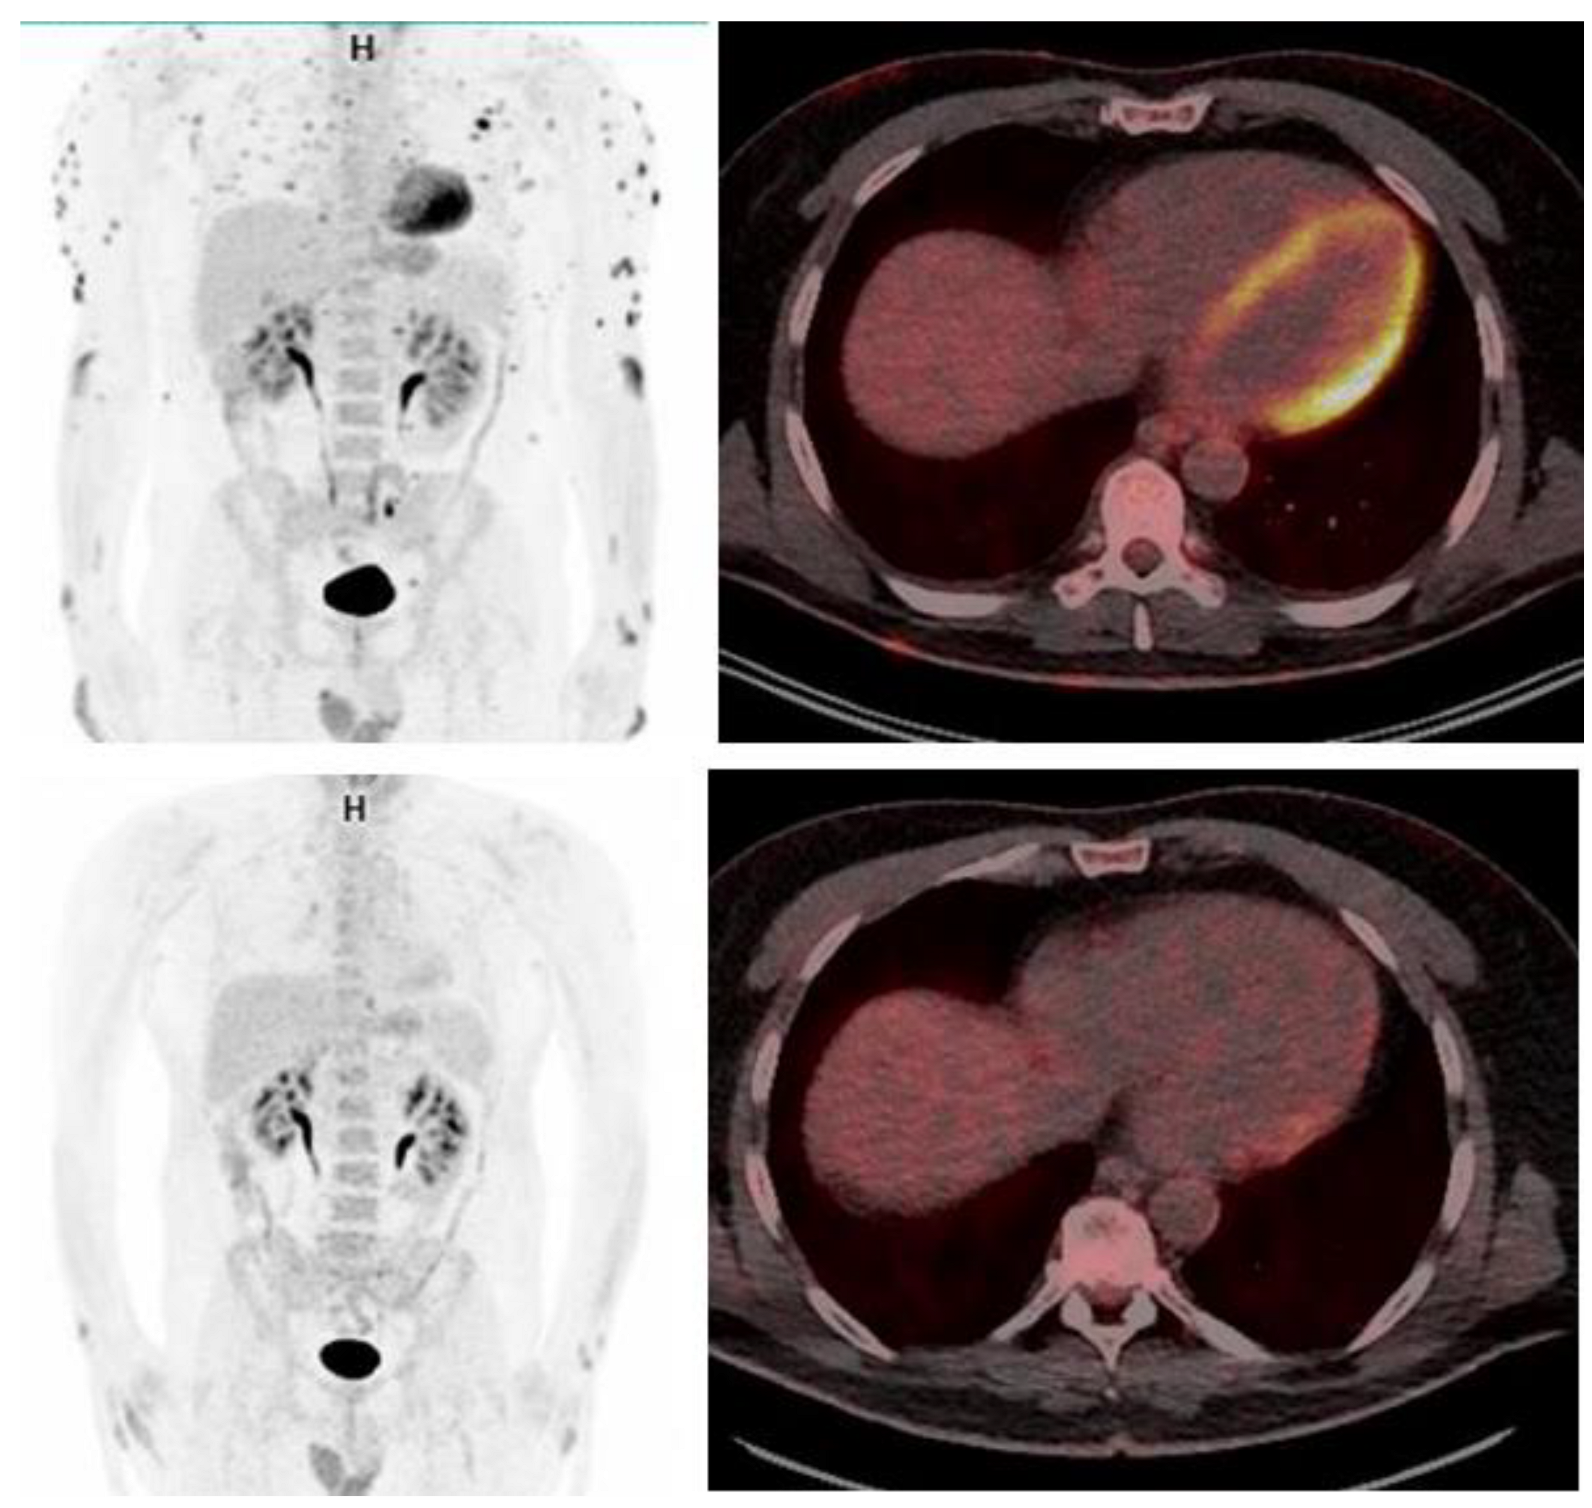

2. Case Report